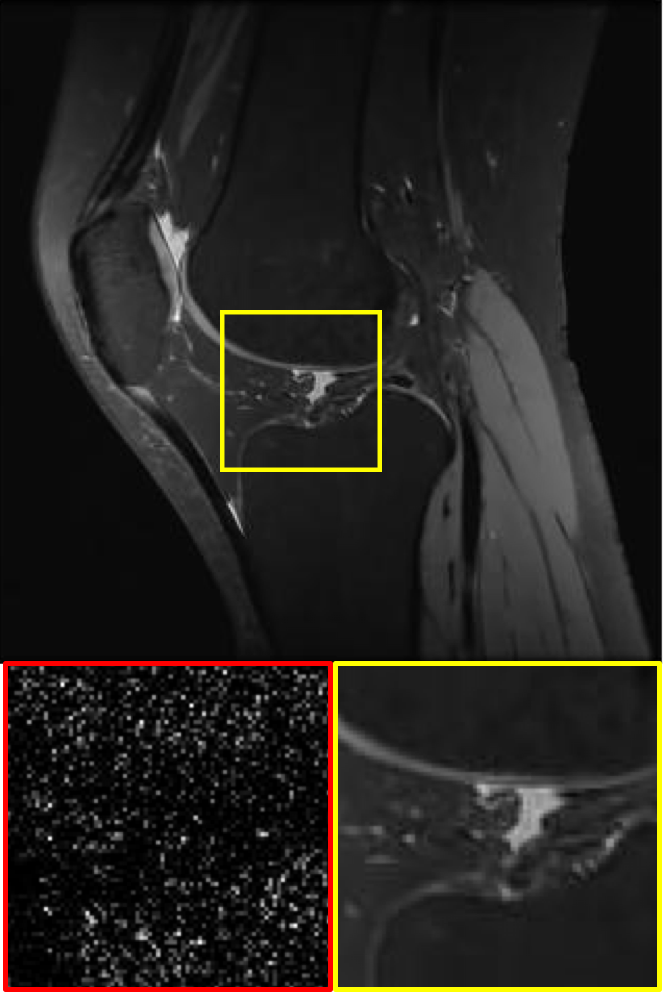

CS MR measurement matrix

LDAMP SURE was applied to CS-MRI reconstruction problem to demonstrate its generality and to show its performance on images that contain structures different from natural image dataset. We compared LDAMP SURE with state-of-the-art BM3D-AMP-MRI algorithm [16] for CS-MR image reconstruction along with TVAL3, BM3D-AMP, and dictionary learning method or DL-MRI [34]. Average image recovery PSNRs and run times are tabulated in Table 3. Figure 5 shows that our proposed method yielded state-of-the-art performance, close to the ground truth. The results reveal that proposed LDAMP SURE-T outperforms existing algorithms in all sampling ratios.

Ground truth

TVAL3

BM3D-AMP

NLR-CS

LDAMP SURE

LDAMP SURE-T

Ground truth

TVAL3

BM3D-AMP

DL-MRI

BM3D-AMP-MRI

LDAMP SURE-T